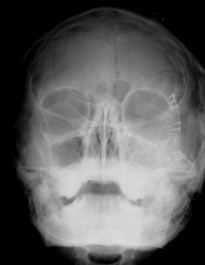

Рентгенограммы придаточных пазух носа той же больной после операции

На рентгенограмме отмечается уменьшение прозрачности верхнечелюстной пазухи слева, а также нарушение непрерывности скулоальвеолярного гребня. В аксиальной проекции видна деформация скуловой дуги.